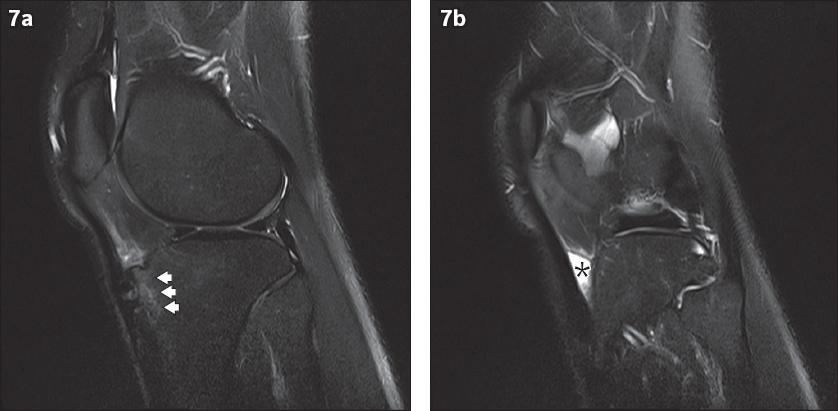

Fig. 7

A 19-year-old man presented with pain at the anterior aspect of the knee. Sagittal proton density fat-saturated turbo spin-echo MR images show (a) fragmentation and increased signal intensity of the tibial tuberosity (arrowheads) compatible with Osgood-Schlatter disease, and (b) a triangular fluid signal collection deep to the distal patellar tendon (asterisk). This is the typical appearance of deep infrapatellar bursitis.